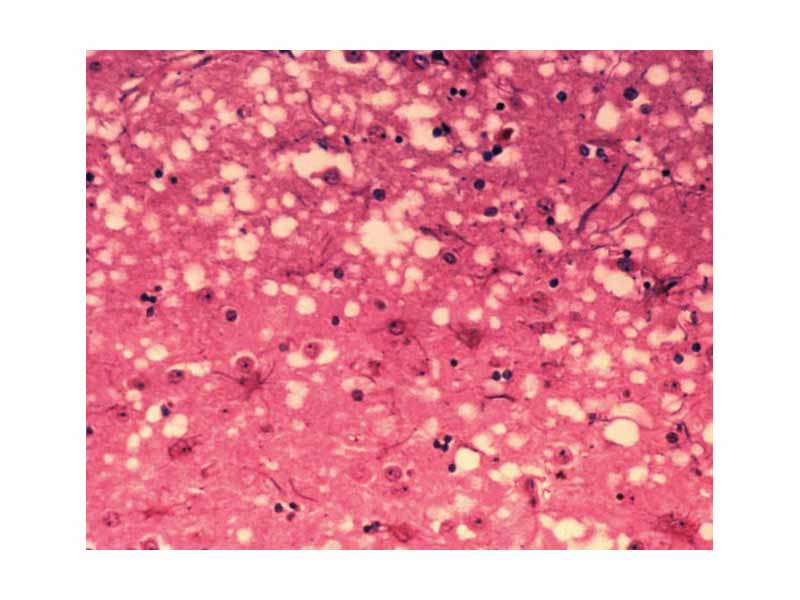

This micrograph of brain tissue reveals the cytoarchitectural histopathologic changes found in bovine spongiform encephalopathy. The presence of vacuoles, i.e. microscopic holes in the gray matter, gives the brain of BSE-affected cows a sponge-like appearance when tissue sections are examined in the lab.